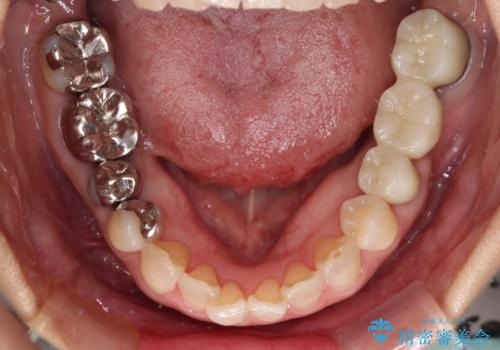

- 近医にて奥歯の抜歯が必要と言われたとのことで来院された患者様です。

診断の結果、奥歯は歯根が破折しており、抜歯が必要な状況でした。

インプラントあるいはブリッジによる補綴治療が考えられましたが、前後の歯が大きな銀歯であったため、オールセラミックブリッジにより3本の歯を審美的に仕上げることとしました。